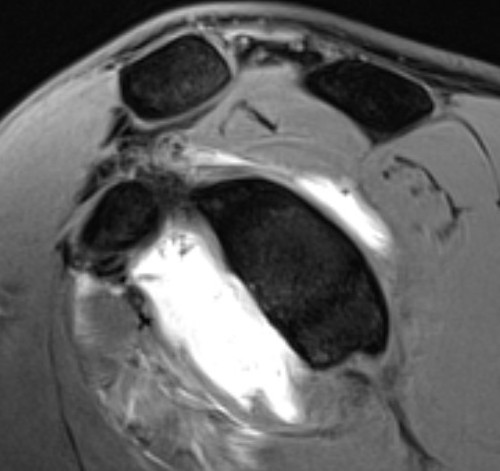

Hill Sachs variations